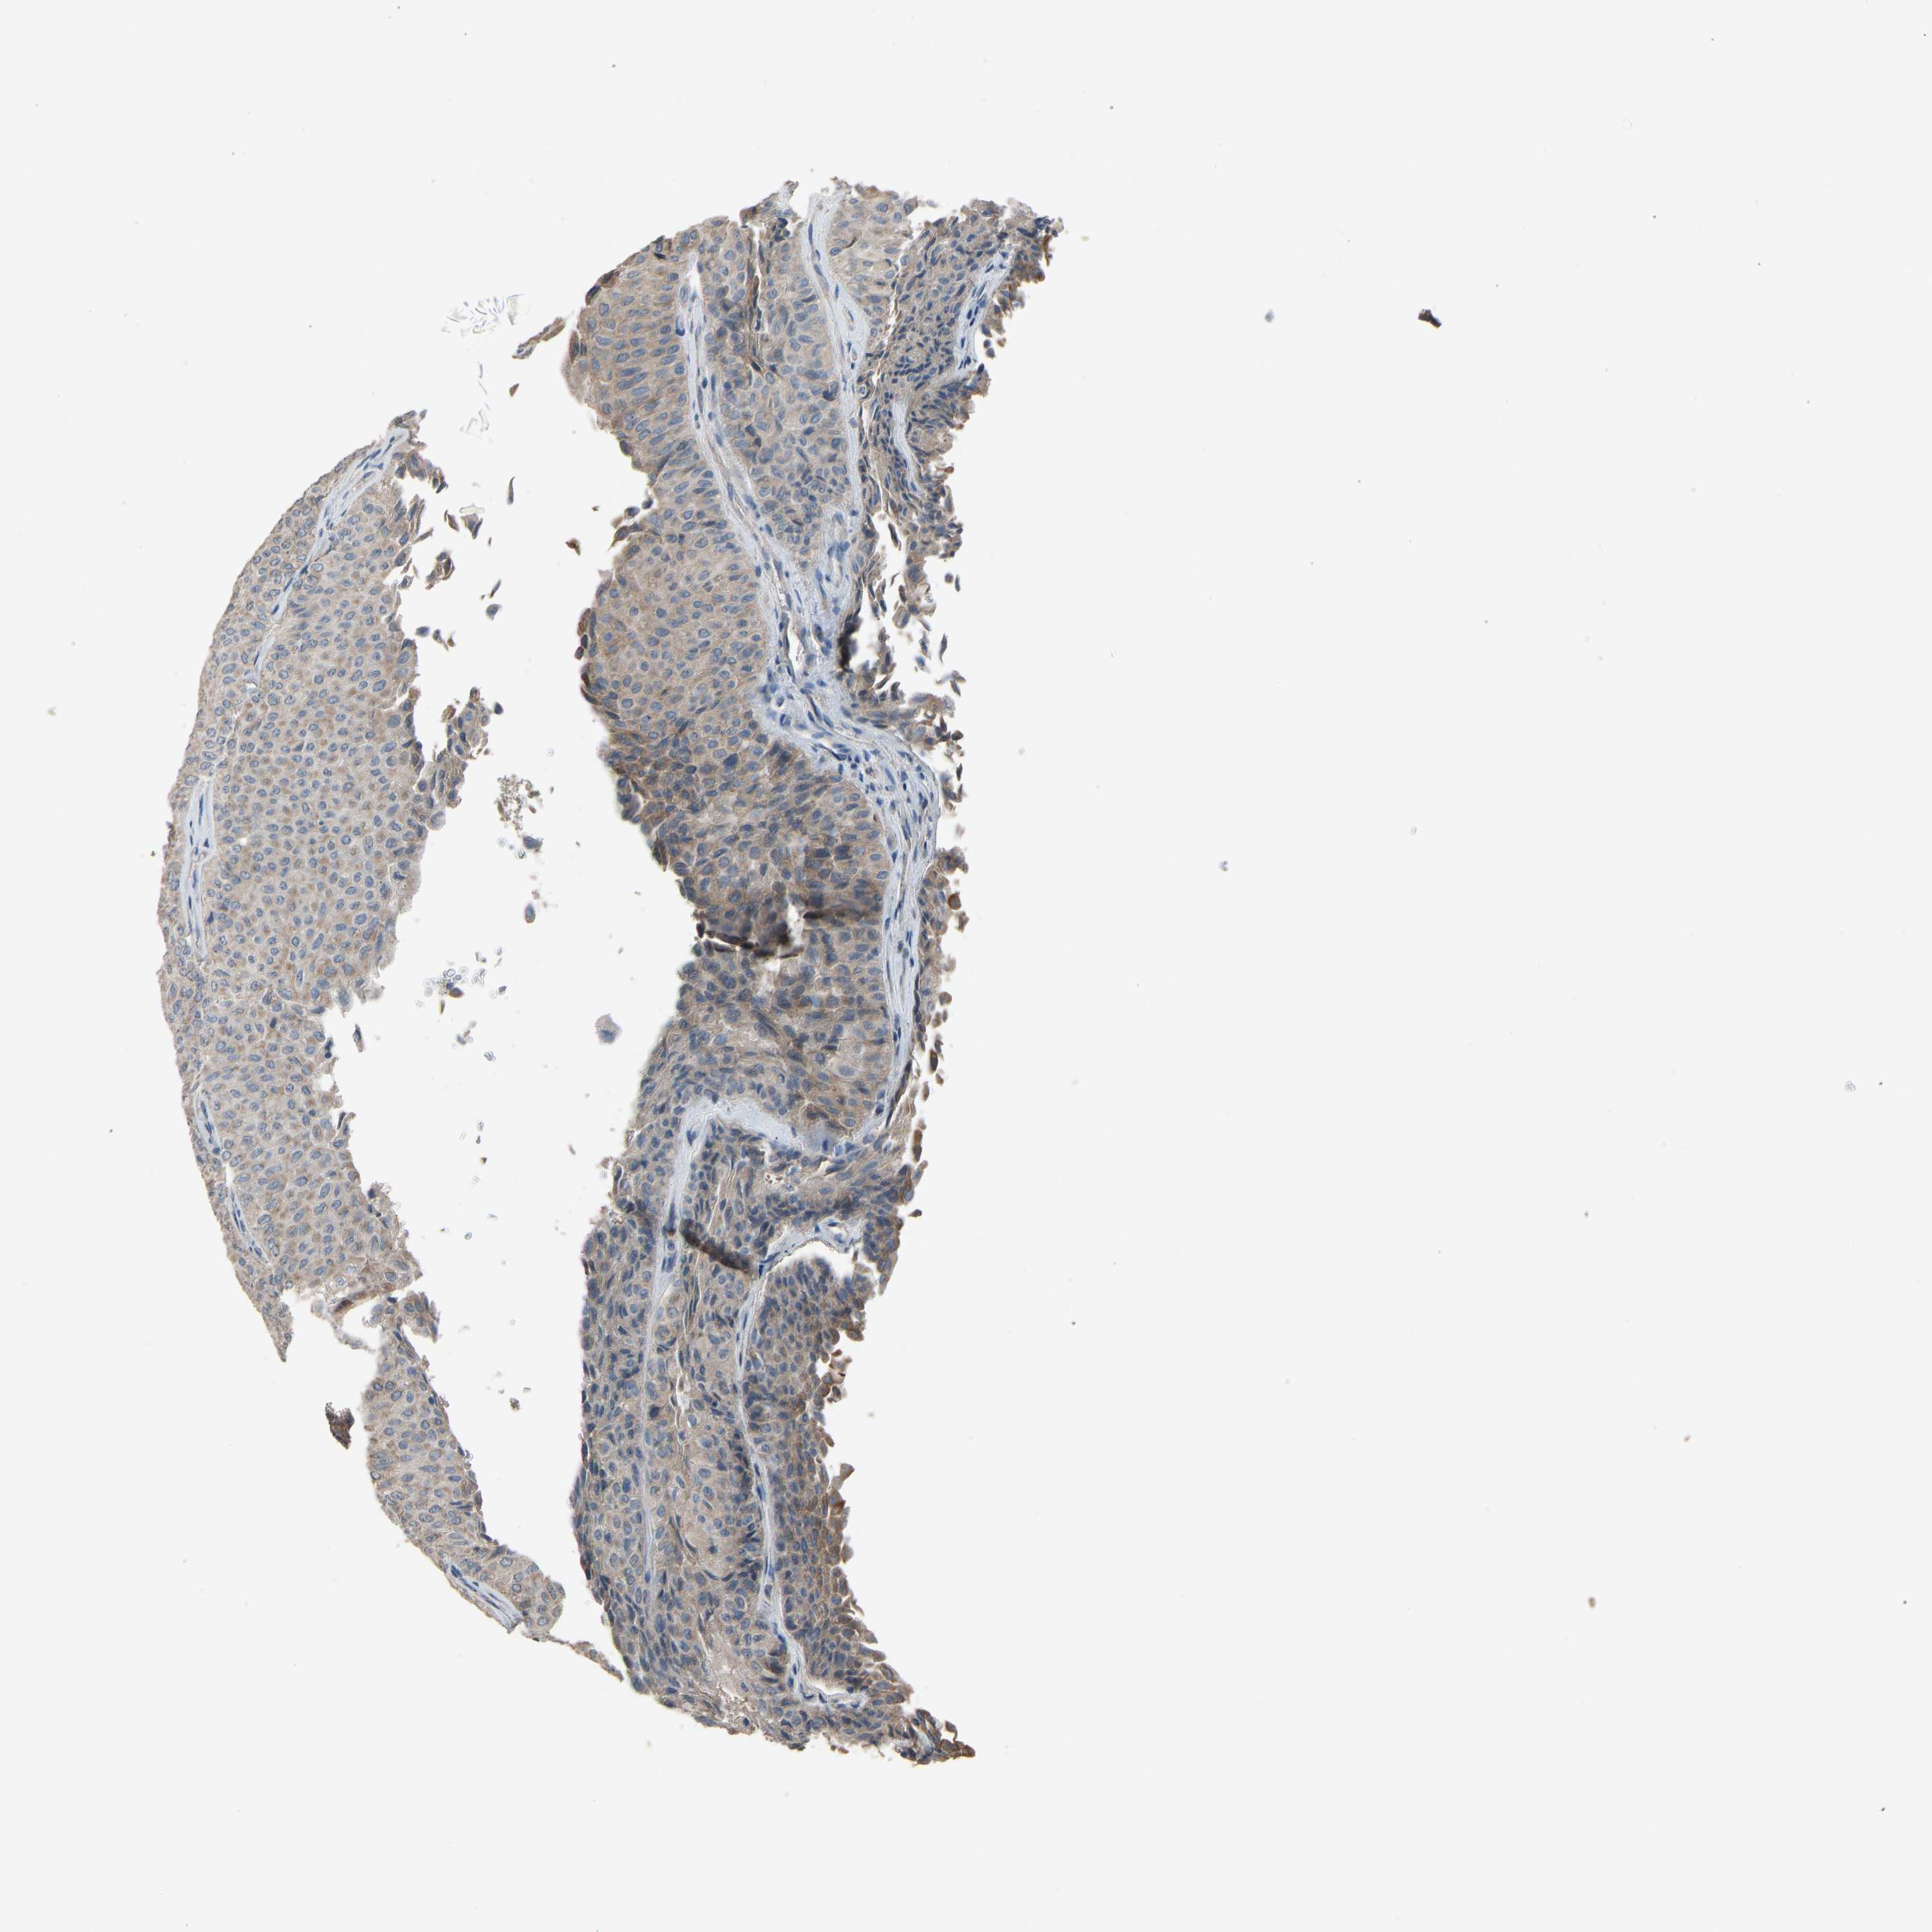

UROTHELIAL CANCER - Protein expressioni

A mouse-over function shows sample information and annotation data. Click on an image to view it in a full screen mode. Samples can be filtered based on level of antibody staining by selecting one or several of the following categories: high, medium, low and not detected. The assay and annotation is described here.

Antibody stainingi

Antibody staining in the annotated cell types in the current human tissue is reported as not detected, low, medium, or high, based on conventional immunohistochemistry profiling in selected tissues. This score is based on the combination of the staining intensity and fraction of stained cells.

Each image is clickable and will lead to virtual microscopy that enables deeper exploration of all samples and also displays staining intensity scores, fraction scores and subcellular localization as well as patient and tissue information for each sample.

Antibody HPA008257

Antibody CAB018971

Urothelial carcinoma, Low grade

Urothelial carcinoma, High grade